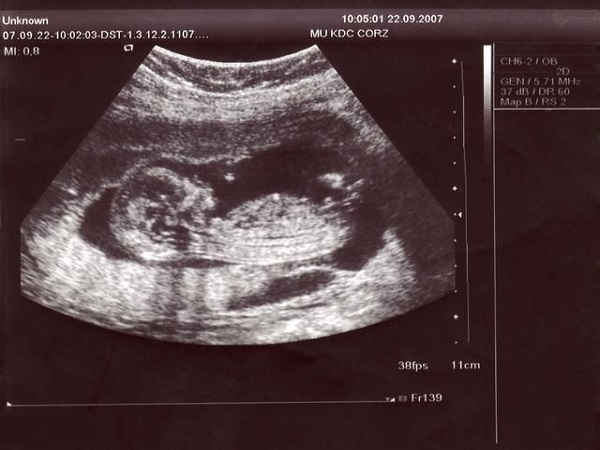

现在的医疗技术已经越来越先进和发达了,要想知道孩子的性别其实并不难,但是为了保证男女平等,所以国家禁止了一切非医学需要的胎儿性别鉴定。但是整个孕期女性都需要做各种各样的检查,其中四维检查就是非常重要的,网传通过四维检查中胎儿的脊柱看男女是非常准确的,通过脊柱的位置、排列方式等就能够预测出生男生女,因为男孩和女孩的脊柱是由一定区别的,有相关需求的朋友可以了解一下。

四维检查是孕中期女性需要做的一项排畸检查,主要是为了进一步了解胎儿的各器官是否发育正常,有无异常情况。通过四维彩超是能够清晰的看到宝宝的眼、耳、口、鼻等各个器官,所以也是可以看到胎儿性别的。但是医生并不会将其告知父母,但是民间认为通过四维检查报告单中胎儿的脊柱也是可以看出男女的,而且已经有不少宝妈进行了尝试和验证。

孕中期的时候胎儿的脊柱已经基本发育完全,网传男孩和女孩的脊柱是有一定区别的,所以通过脊柱的位置和排列方式可以判断出怀的是男孩还是女孩,下面就为大家详细介绍一下脊柱看男女最准的方法。

1排列方式:通常认为胎儿的脊柱如果呈串珠形、排列比较整齐的话,那么怀的就是男孩,如果脊柱是两条平行的光带的话,就说明怀的是女宝宝;2脊柱和尾骨的角度:一般来说,男孩的脊柱和尾骨之间的夹角会比较大,会大于30度,反之如果脊柱和尾骨之间是平平的,夹角小于30度的话,怀的就是女宝宝;3脊柱尾部:如果孕妈妈怀的是男宝宝的话,那么四维单子上宝宝的脊柱下端就会有个小尾巴,是翘起来的,但是如果怀的是女宝宝的话,那么就没有小尾巴是平的。